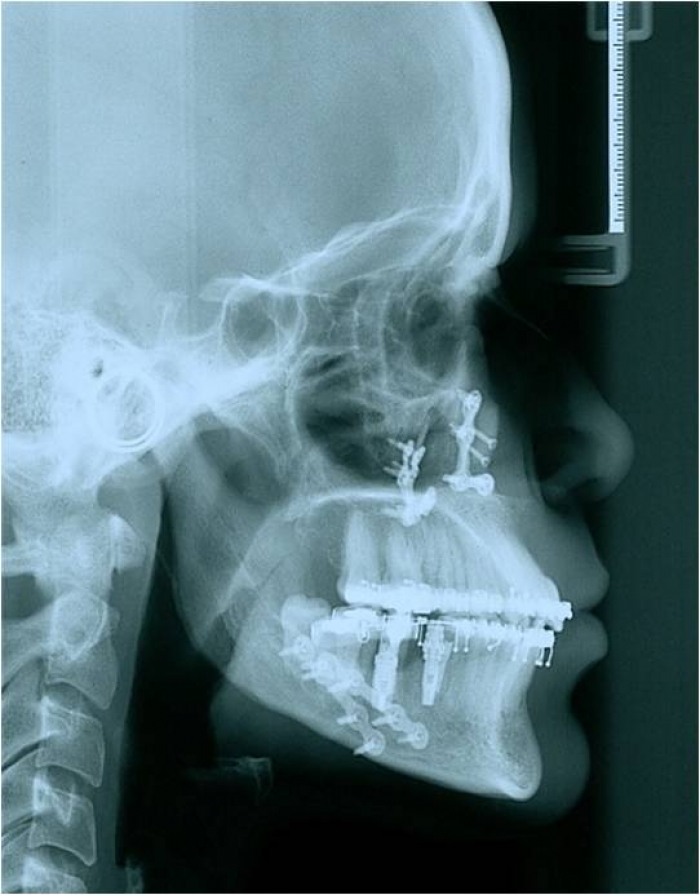

Telerradiografia após a cirurgia